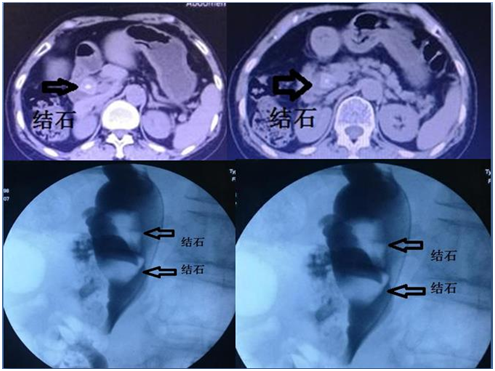

65岁的荣女士十年前因胆囊结石、胆总管结石行胆囊切除并胆总管取石术,术后恢复良好。近几天来,荣女士感觉右上腹疼痛,疼痛越来越重,不能忍受,就诊于当地医院,CT检查显示:肝总管2枚2.5cm大小的结石。因荣女士以前做过外科取石手术,术后粘连瘢痕形成,胆总管远端狭窄,再次开刀手术风险性高、粘连伤口不易愈合,易发生胆漏,而被放弃外科手术治疗。荣女士及家人为此焦急万分,四处打听有无更好治疗方法。经多方面咨询后,听说介入治疗不用开刀,伤口只有针眼大,能取胆总管内结石,于是找到了取石经验丰富的朱亮副主任医师,并进行会诊,会诊结果:可以行介入取石。

因结石比较巨大,因此治疗起来比较困难,两块结石上下重叠,给抓捕带来困难。首先先使两块石头分离,逐个将其抓捕并粉碎。其次再将粉碎的结石推入肠道,又因为患者以前做过手术,胆总管远端粘连狭窄,结石只有粉碎到足够小才能被推到肠道,又给手术增加了难度。朱亮副主任医师、王宏学主治医师联合应用多种介入技术,将结石推入肠道,术后患者恢复良好,得到了患者及家属的高度评价。